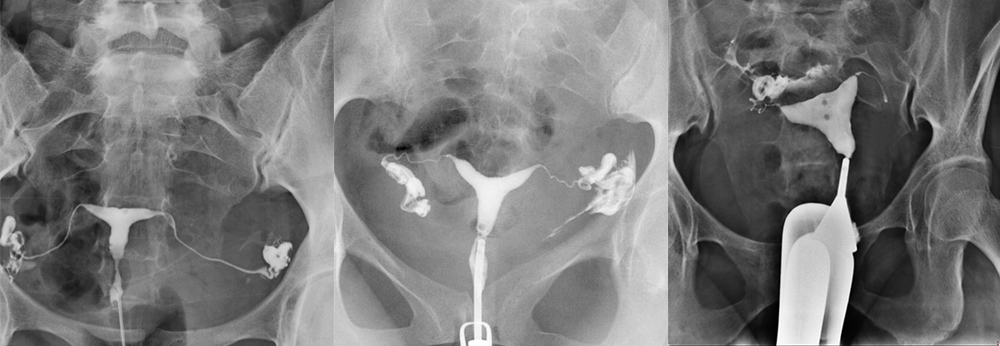

At least four spot radiographs should be taken

The first image ( Figure 1a) is obtained during early filling of the uterus and is used to evaluate any filling defects or contour abnormalities. Small filling defects are best seen at this stage. The second image (Figure 1b) is taken when the uterine cavity is completely filled. Although small filling defects can be hidden when the uterus is well opacified, it is at this stage that the shape of the uterus is best evaluated. The third image (Image 1c) is obtained to show and evaluate the fallopian tubes. The fourth image (Figure 1d ) should show the free intraperitonal spread of the contrast agent. Additional spot radiographs may be taken to detect any abnormalities observed. Oct. Oblique images can be taken when necessary to better view the tubes and prevent overlaps. At the end of the study, if the balloon closes the area where it was placed at the first placement, a radiography is obtained after deflating the balloon to evaluate the uterine lower segment. We do not use the tenaculum; if it is necessary to pull the uterus, we do this by gently pulling down the HSG catheter.

Image 1a. Spot radiography obtained at the early filling stage of the uterus. Small filling defects are best seen at this stage.

Image 1b In a radiograph obtained after the uterus is completely filled with a contrast agent, the initial parts of both fallopian tubes become opaque. Like images obtained at the early filling stage of the uterus, images obtained at full uterine distension allow the evaluation of defects and contour abnormalities. However, small filling defects may be hidden when the uterus is completely full.

Figure 1c clearly shows the interstitial, isthmic and ampullary parts of both fallopian tubes.

Figure 1d It is seen that the contrast agent is poured from the fallopian tubes into the intraperitoneal area. In this case, the shedding shows the outward curve of the uterine fundus(arrow).